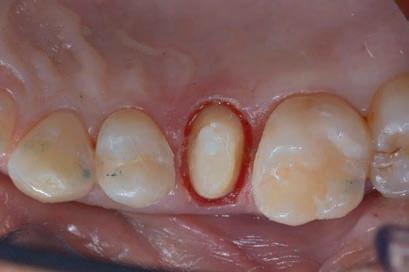

Figure 8: Recovery 2 weeks after surgery. Note the disappearance of post-surgical edema. The provisional crown was placed after two weeks to allow the formation of an epithelial-connective seal in the area. Figure 9: Prosthetic preparation of the dental element with BOPT technique. Note the minimal aggressiveness in the dental groove, recently traumatized by surgery. Figure 10: First relining in acrylic resin of the provisional crown in PMMA obtained by digital scanning of the arches, suitable to condition the tissues after only 4 weeks from the operation, taking advantage of the reparative thrust that follows a periodontal surgery.

Figure 11: Provisional crown in PMMA finished and positioned. Composite reconstructions on teeth 24 and 26 have been replaced in order to construct correct contact points with the final crown Figure 12: Final radiography after positioning of the endodontic post, composite reconstruction and insertion of the provisional crown in PMMA. Note the distance between the edge of the cement used to fix the crown, more radiopaque than PMMA, and the new bone ridge created with periodontal surgery.

After the restoration, the tooth was prepared with the BOPT technique5-6 . A provisional PMMA crown, obtained with an optical scan done before the preparation of the element with a AADVA IOS100 scanner (GC), was placed. During this phase the obsolete restorations of the teeth 24 and 26 were replaced. (Figs. 9-12)